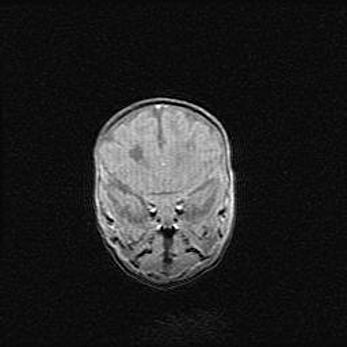

Наружная гидроцефалия с возможной атрофией височных областей.

Возраст: 28 дней

Вес: 3670 г

Пол: мужской

Окружность головы: 38 см

Срок гестации: 40 недель

Гидроцефалия головного мозга у новорожденных – это заболевание, которое характеризуется скоплением избыточного количества спинномозговой жидкости в желудочковой системе головного мозга в результате затруднения её перемещения от места выработки к месту поглощения в кровеносную систему или вследствие нарушения абсорбции. При открытой наружной форме гидроцефалии у новорожденных расширяются и переполняются субарахноидные пространства.

При нормотензивных  формах,  которые,  как  правило,  являются  следствием  перенесенных ишемических  повреждений  паренхимы  мозга,  возможно  сочетание микроцефалии  с нормотензивной гидроцефалией. В основе данных изменений лежит атрофия больших полушарий с преимущественной  локализацией  в  лобно-височных  областях.